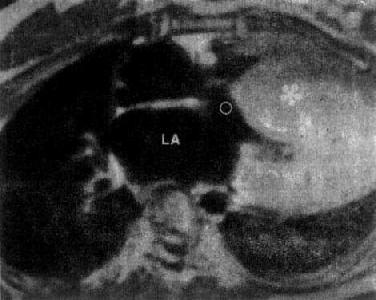

图3-2-28 特发性心肌病

MRI是无创伤性检查方法,对下述疾病有诊断价值:①大血管病:主动脉夹层动脉瘤,能显示真假腔和内膜片;主动脉瘤,可见主动脉腔扩大,壁薄及瘤内血栓;主动脉的异常,如缩窄和扩张以及腔静脉的狭窄和梗阻。②先天性心脏病:房室间隔缺损、主动脉缩窄、动脉导管未闭和复杂性先天性心脏病。③心肌病变;心肌梗死、室壁瘤(图3-2-27)、瘤内血栓形成、特发性心肌病(图3-2-28)。④心脏肿瘤:良性粘液瘤、恶性纤维组织细胞瘤、血管肉瘤和肌肉瘤等。⑤心包病变:心包积液,心包肥厚和心包肿瘤等。